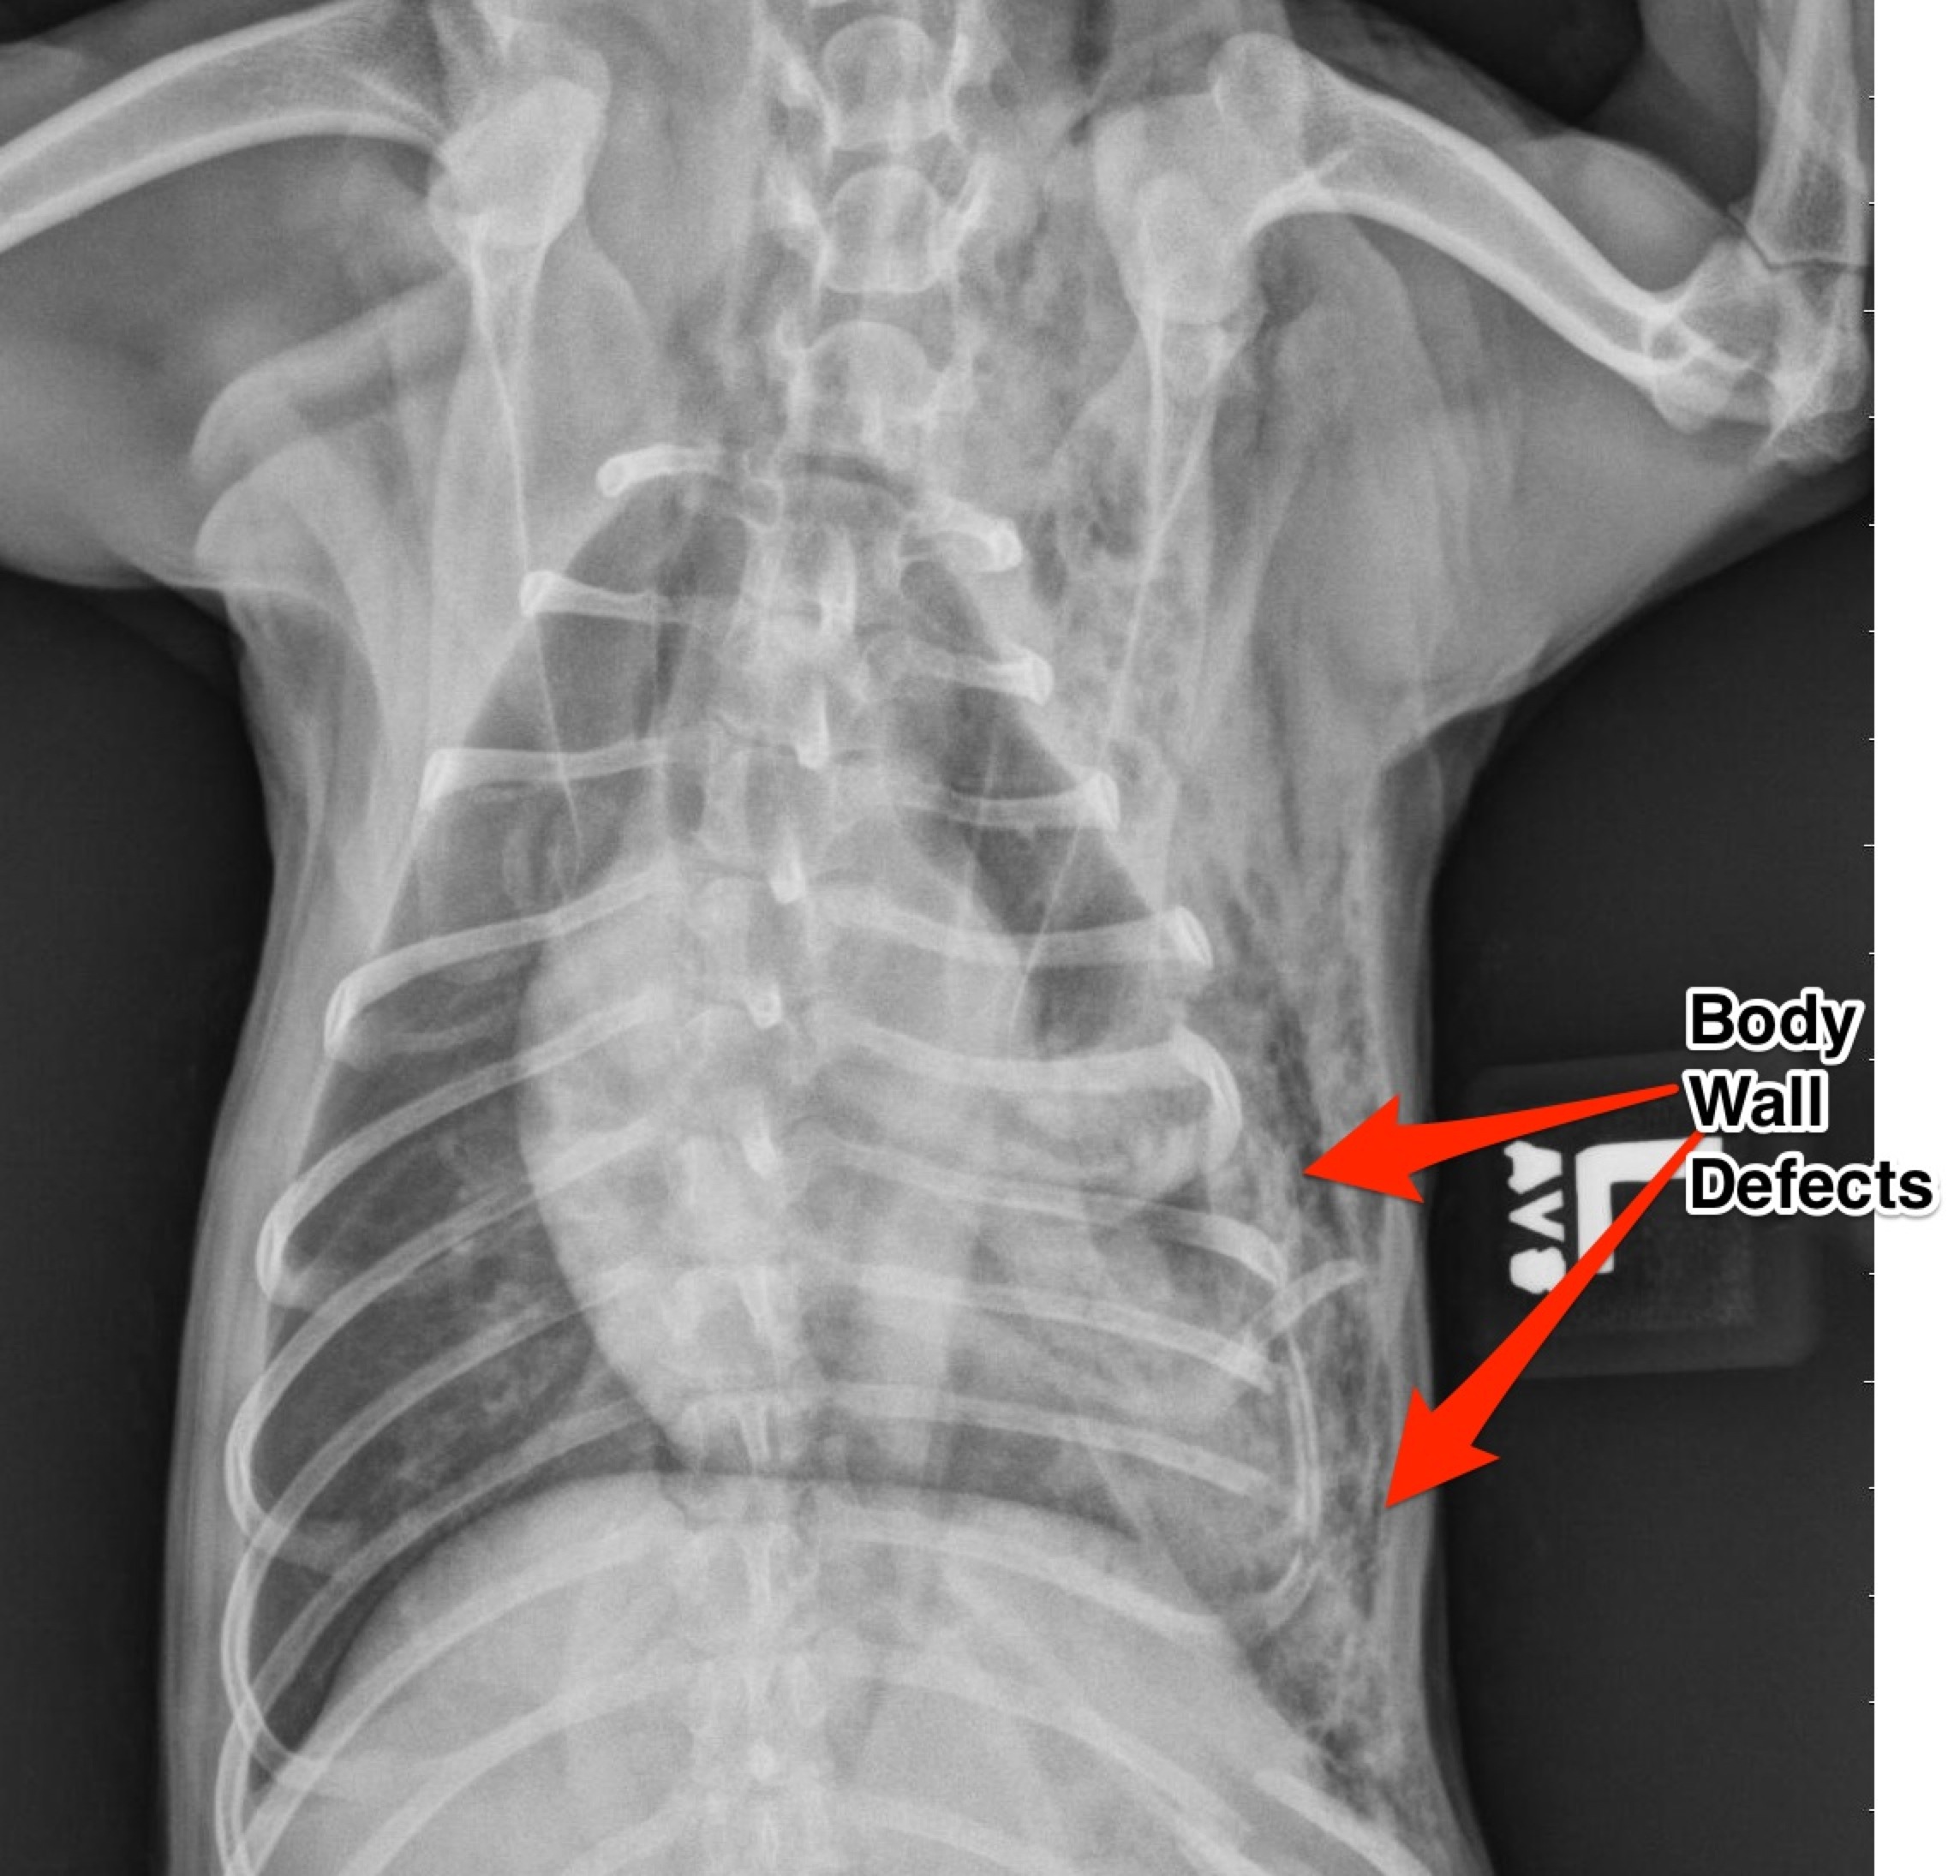

Smokey was transferred to the surgery department from the overnight emergency service after being attacked by a larger dog the night before. His injuries were multiple and severe. He sustained multiple bite wounds over his thoracic and abdominal body cavities. Thoracic radiographs revealed multiple left sided rib fractures and multiple defects (tears) into the chest wall. The bite wounds over the abdomen were superficial with no evidence of penetration in the abdomen.

Note the multiple rib fractures and the multiple thoracic wall defects.